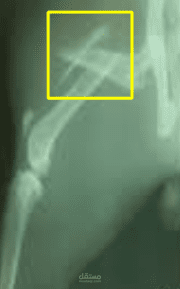

يقدم هذا المشروع حلًا شاملاً ومتكاملًا (End-to-End) للتصنيف الآلي لكسور عظمة الفخذ (Femur) لدى الكلاب.

يهدف المشروع إلى مساعدة الأطباء البيطريين في تشخيص أنواع الكسور من صور الأشعة السينية (X-ray) بدقة فائقة، وذلك من خلال الاستفادة من أحدث تقنيات الرؤية الحاسوبية (Computer Vision) والتعلم العميق (Deep Learning).

آلية العمل: يقوم النظام بمعالجة صور الأشعة الأولية، ويعزل عظمة الفخذ موضع الاهتمام، ثم يستخدم مجموعة من الشبكات العصبية التلافيفية القوية (CNNs) لتقديم تصنيف سريع وموثوق لنوع الكسر.